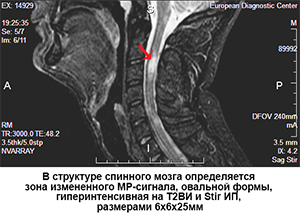

Диагностика РС по МРТ – это как поиск иголки в стоге сена. Врачу нужно внимательно изучить множество снимков, выявить и оценить очаги поражения (бляшки), которые могут быть очень маленькими и трудноразличимыми. Этот процесс занимает много времени и сил, а человеческий фактор может привести к ошибкам и задержкам в диагностике. Мы столкнулись с проблемой: как можно автоматизировать и улучшить процесс оценки РС по МРТ с помощью ИИ?

Наша система анализирует последовательные МРТ-снимки пациента, сделанные в разное время, и автоматически выявляет изменения в очагах поражения. Она может определить, появились ли новые очаги, увеличились ли старые очаги в размере или уменьшились ли они. Эта информация помогает врачам оценить эффективность лечения и принять решение о его корректировке.